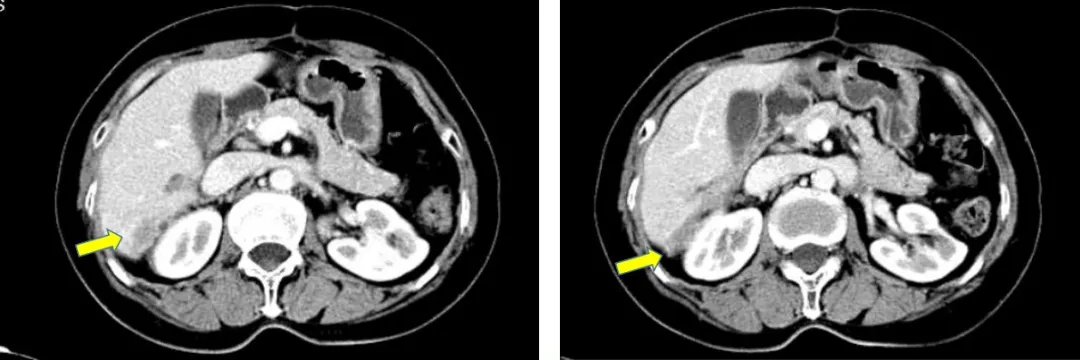

CT检查结果